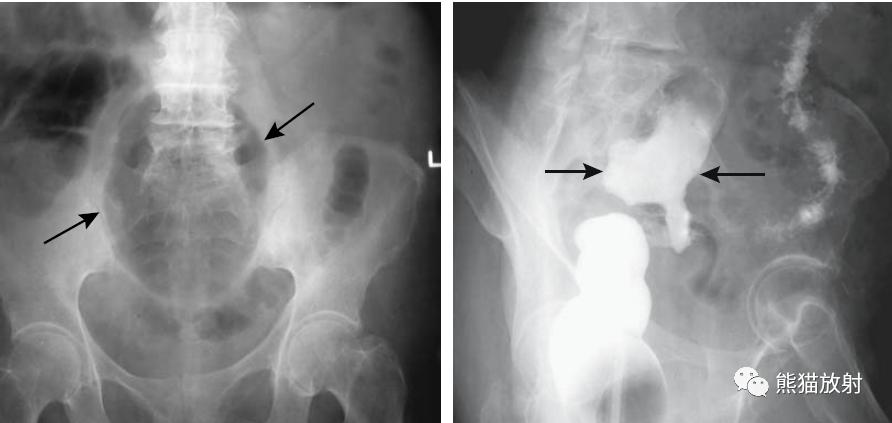

乙状结肠扭转。消化道造影侧视图可见乙状结肠局部走行扭曲(箭头)。

结-结肠肠套叠(箭头)。此例病因很罕见,为结肠子宫内膜异位。

结-结肠肠套叠,由盲肠癌所致。钡灌肠显示横结肠中的肠套叠(箭头),在进一步的压力下,肠套叠移位至升结肠。